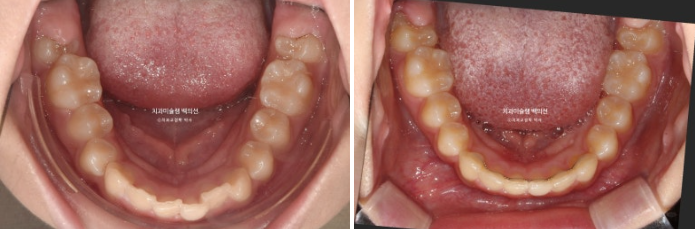

24년 2월부터 9월까지 장치를 모두 낀 후 모습입니다.

중심선이 아직 맞지는 않지만 과개교합이 해소가 되었습니다.

어금니 교합이 아직 완벽하진 않습니다.

배열은 좋습니다.

중심선, 교합 개선을 위해 추가장치 제작에 들어갔습니다